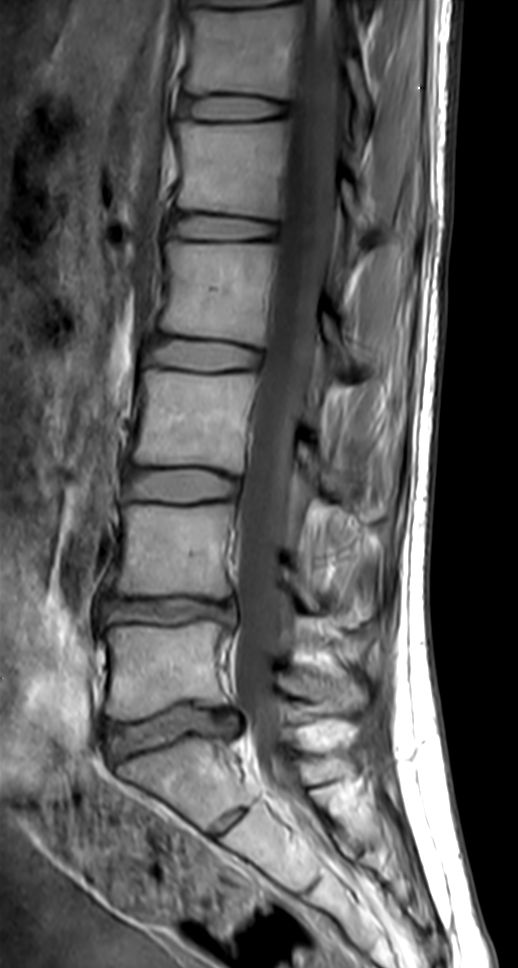

Total lumbar spine exam, showing excellent image quality in only 9:20 minutes.

Sagittal T2w TSE